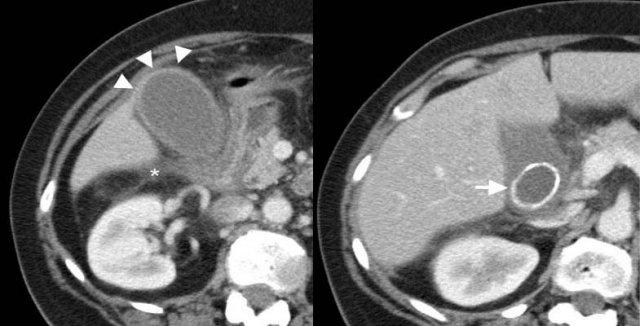

Viêm túi mật u hạt vàng. TRÁI: Siêu âm cho thấy thành túi mật dày rõ với các nốt giảm âm trong thành (đầu mũi tên) và sỏi trong lòng (mũi tên). PHẢI: CT có thuốc cản quang cho thấy thành túi mật biến dạng và dày, chứa các nốt giảm tỷ trọng.

Viêm túi mật u hạt vàng

Viêm túi mật u hạt vàng là một thể hiếm gặp của viêm túi mật mạn, đặc trưng bởi quá trình viêm chứa lipid tương tự như viêm thận bể thận u hạt vàng.

Hình ảnh học cho thấy thành túi mật dày rõ, thường chứa các nốt trong thành giảm âm trên siêu âm và giảm tỷ trọng trên CT, đại diện cho các ổ áp xe hoặc ổ viêm u hạt vàng.

Các đặc điểm này chồng lấp với ung thư túi mật, khiến việc phân biệt hai thực thể này trước phẫu thuật thường không thể thực hiện được [6].

Viêm túi mật u hạt vàng. Các nốt giảm tỷ trọng (đầu mũi tên) đại diện cho các ổ áp xe. Lòng túi mật chứa nhiều viên sỏi (mũi tên).

Bên trái là hình ảnh của bệnh nhân nam 71 tuổi với viêm túi mật u hạt vàng.

CT có thuốc cản quang cho thấy thành túi mật biến dạng và dày, chứa các nốt giảm tỷ trọng.

Các nốt này đại diện cho các ổ áp xe hoặc ổ viêm.

TRÁI: Ung thư túi mật. Siêu âm cho thấy thành túi mật dày toàn bộ rõ rệt (đầu mũi tên), lấp đầy lòng túi mật. Nhiều viên sỏi túi mật (mũi tên) chỉ ra vị trí có thể của lòng túi mật đã bị lấp đầy. PHẢI: CT có thuốc cản quang cho thấy túi mật thành dày (đầu mũi tên), với khối xâm lấn khu trú vào nhu mô gan lân cận (mũi tên).

Ung thư túi mật

Ung thư túi mật là bệnh ác tính phổ biến thứ năm của đường tiêu hóa, được phát hiện tình cờ trong 1% đến 3% các mẫu bệnh phẩm cắt túi mật [4].

Bệnh thường được phát hiện ở giai đoạn muộn do thiếu các triệu chứng sớm hoặc đặc hiệu.

Ung thư túi mật có nhiều dạng hình ảnh khác nhau, từ tổn thương dạng polyp trong lòng túi mật đến khối xâm lấn thay thế toàn bộ túi mật, và cũng có thể biểu hiện dưới dạng dày thành lan tỏa.

Các phát hiện kèm theo như xâm lấn các cấu trúc lân cận, giãn đường mật thứ phát, và di căn gan hoặc hạch có thể giúp phân biệt ung thư với viêm túi mật cấp hoặc viêm túi mật u hạt vàng [2, 4].

Trong trường hợp không có các phát hiện kèm theo này, có thể không thể phân biệt ung thư với viêm túi mật u hạt vàng.